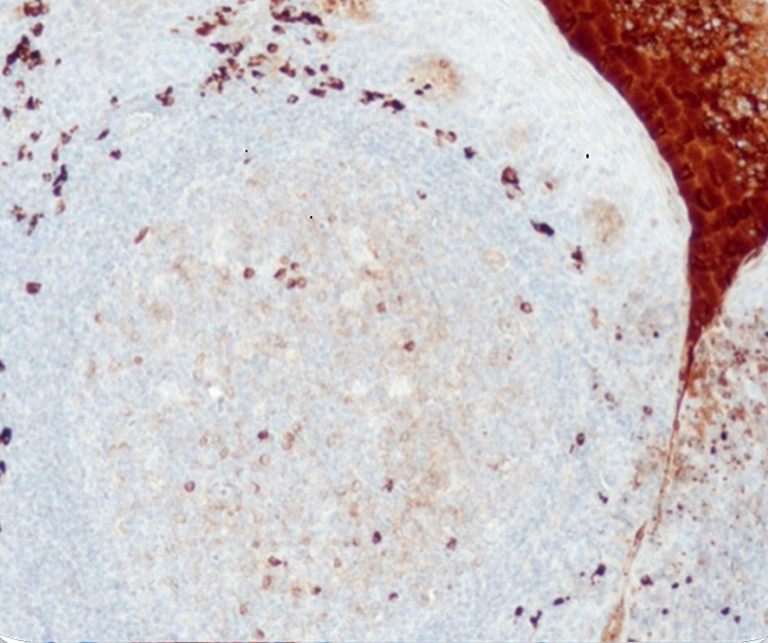

Vascular Pathology

Gastrointestinal (GI) Pathology

General Marker

Breast Pathology

Endocrine Pathology

Gynecological Pathology

Neuropathology

Infection Markers

Lung Pathology

Urinary Tract Pathology

Transplantation Pathology

Soft Tissue Pathology

Hematopathology